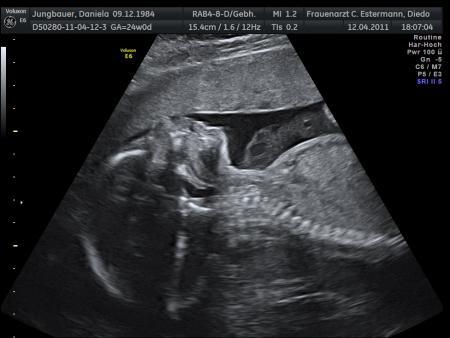

Mäuschen in Denkerpose....

Bild zu ein paar Bildchen vom 3D-Ultraschall..... - Forum für August - Mamis